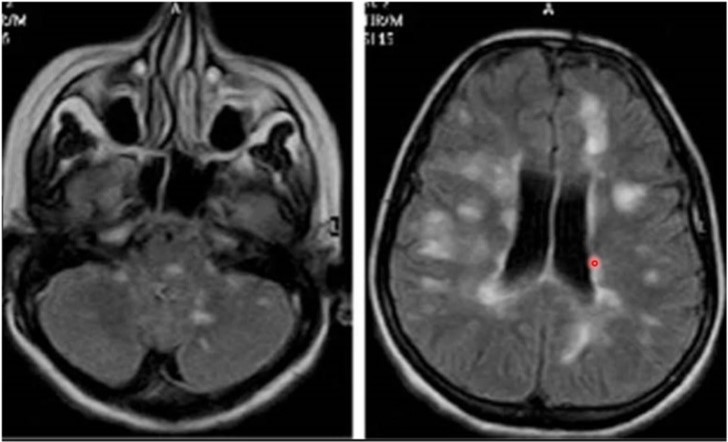

• MR-bild visar inflammationslesioner periventrikulärt och även på lillhjärna och hjärnstam (typiskt)